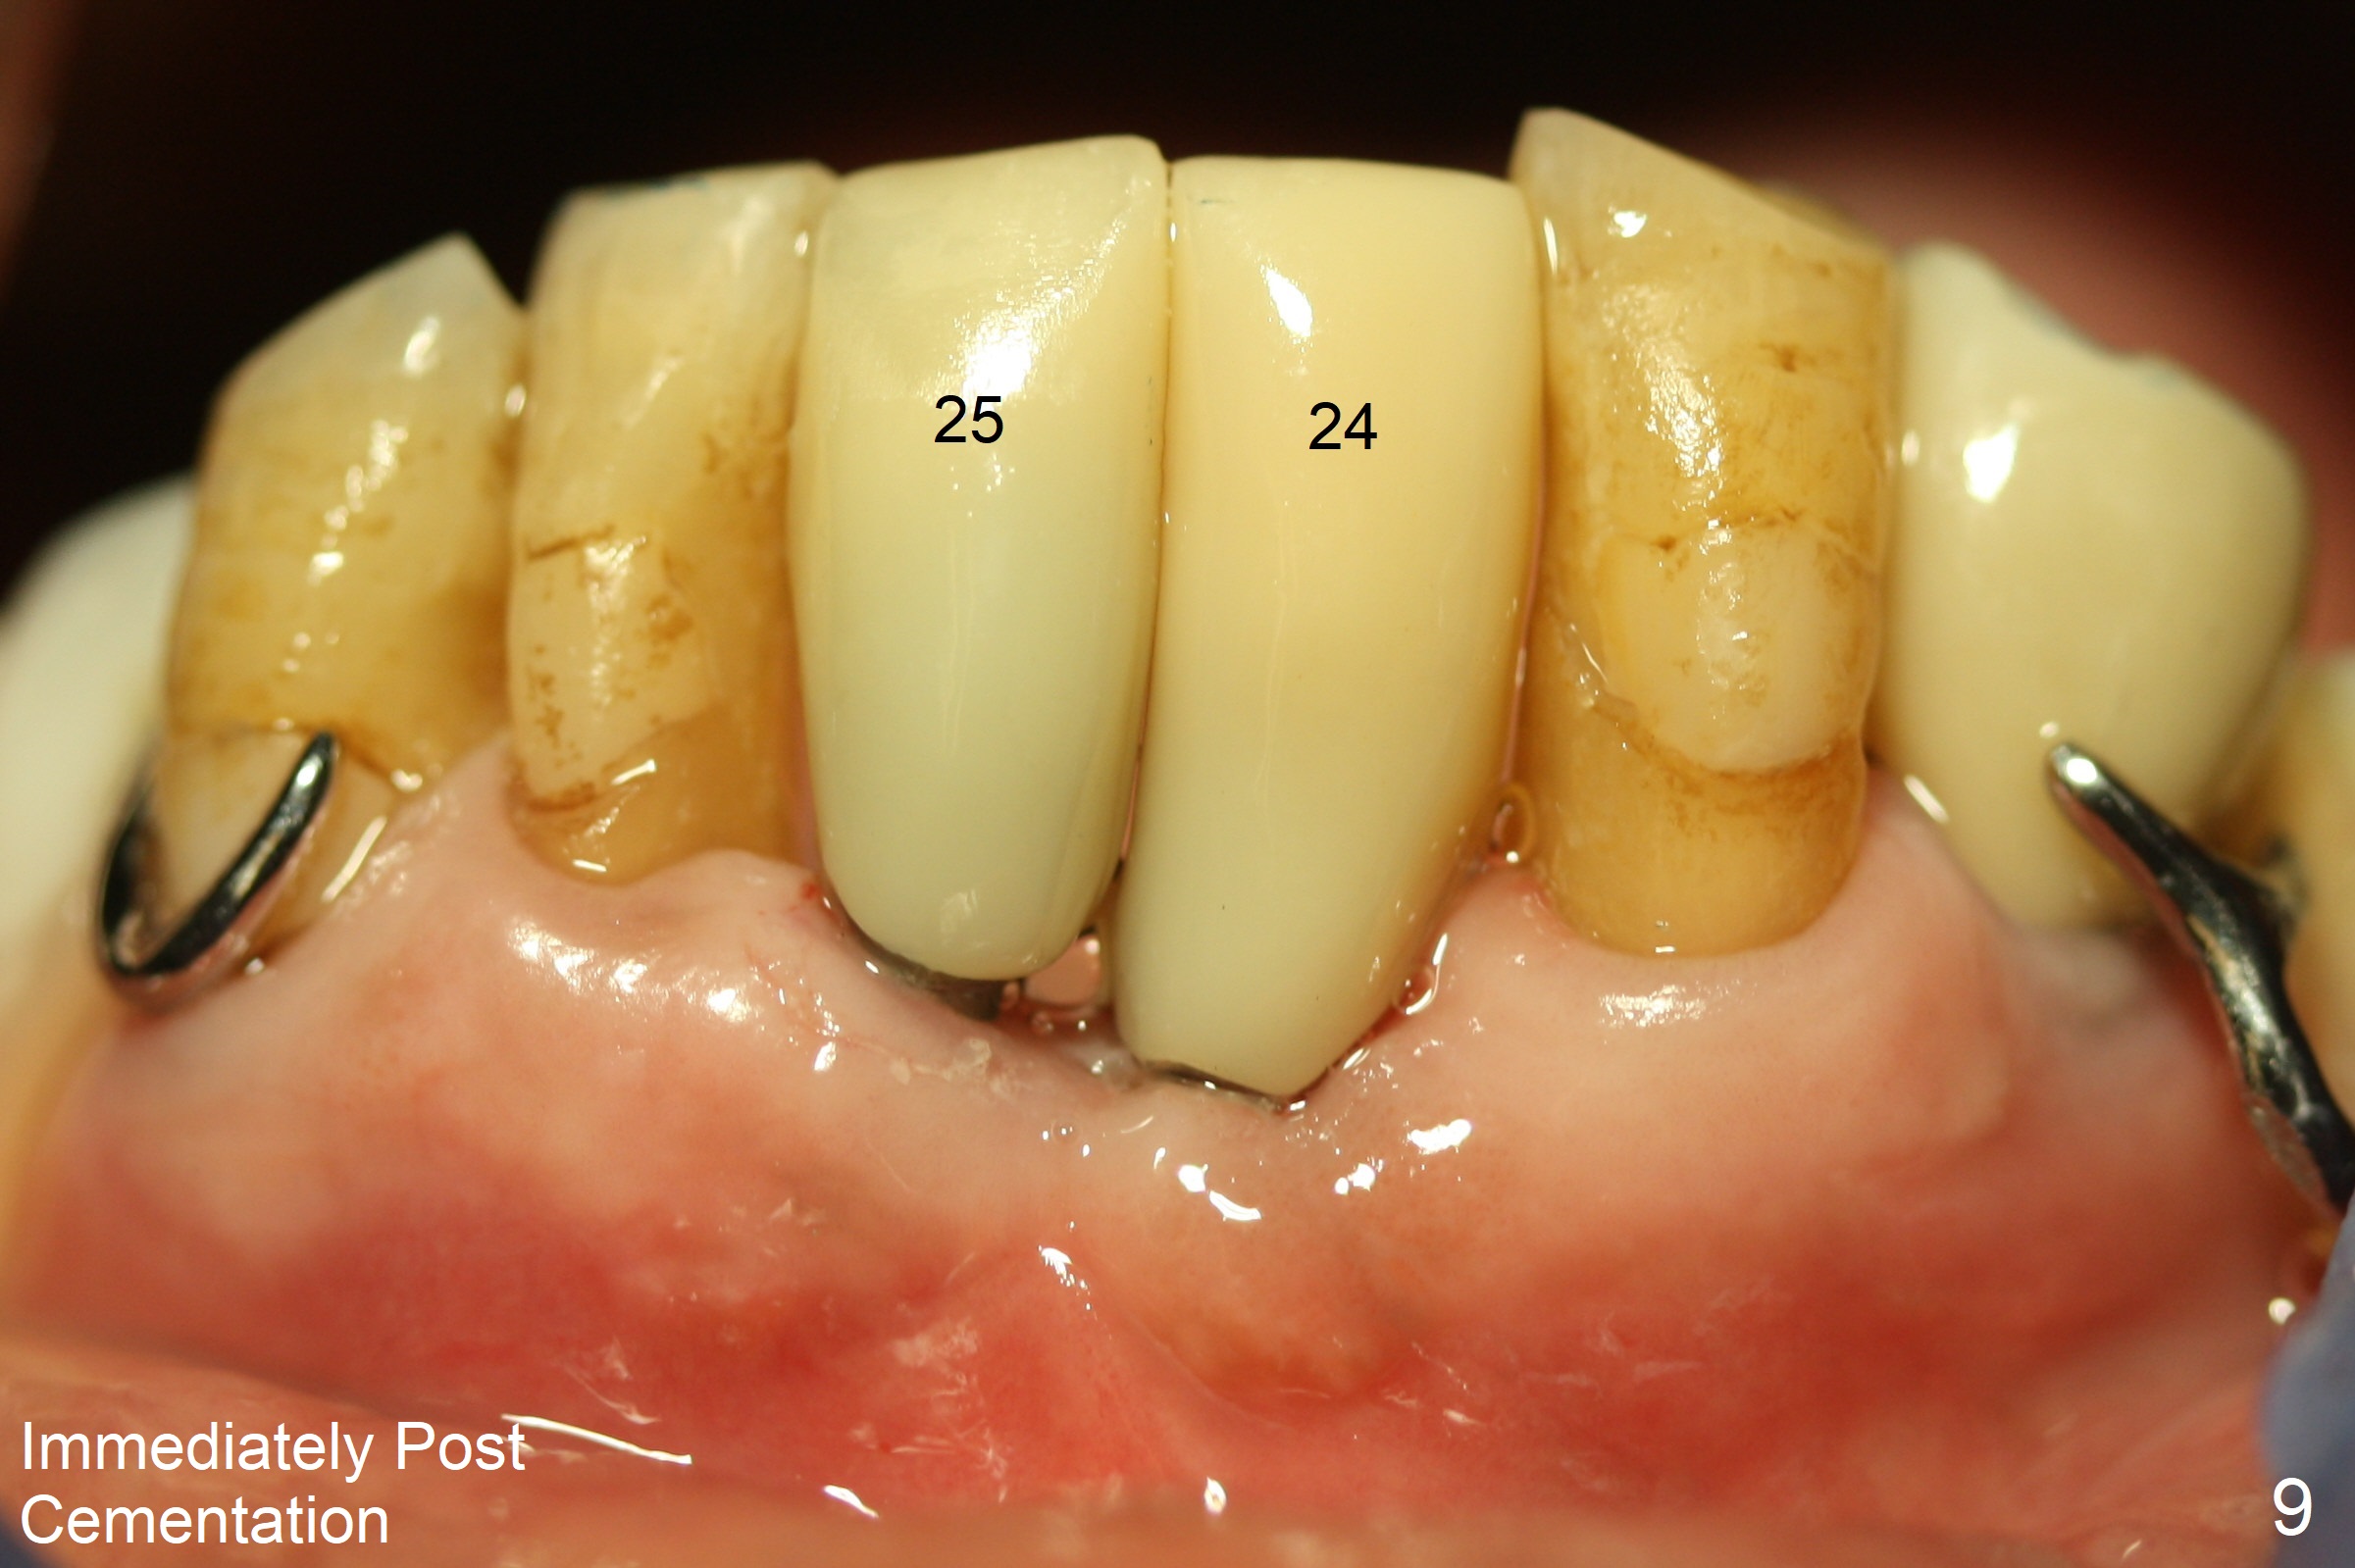

Two and a half months after loss of a 2 mm 1-piece approximately at #23 (Fig.1,2), it appears that the site of #24 (Fig.3 line) is more appropriate because the bone is higher. After removal of the pointed ridge top, osteotomy is initiated with 1.2 mm drill, followed by 1.5 mm one (Fig.4,5). When the 1.5 mm drill is removed, the new osteotomy (Fig.6 *) is mesial to the old one (^). Since the ridge is narrow (Fig.5,6), a 2x14(4) mm 1-piece implant is placed with GBR (Fig.7). Due to overprep, the torque is 20 Ncm. No immediate provisional is fabricated. Instead periodontal dressing is applied around these 2 implants. Two separate provisionals are fabricated when the wound heals. The one at #24 does not stay. The implant at #24 appears to osteointegrate 6.5 months postop (Fig.8). When the crowns are cemented, the margin is supragingival (Fig.9,10). Water Pik is recommended.